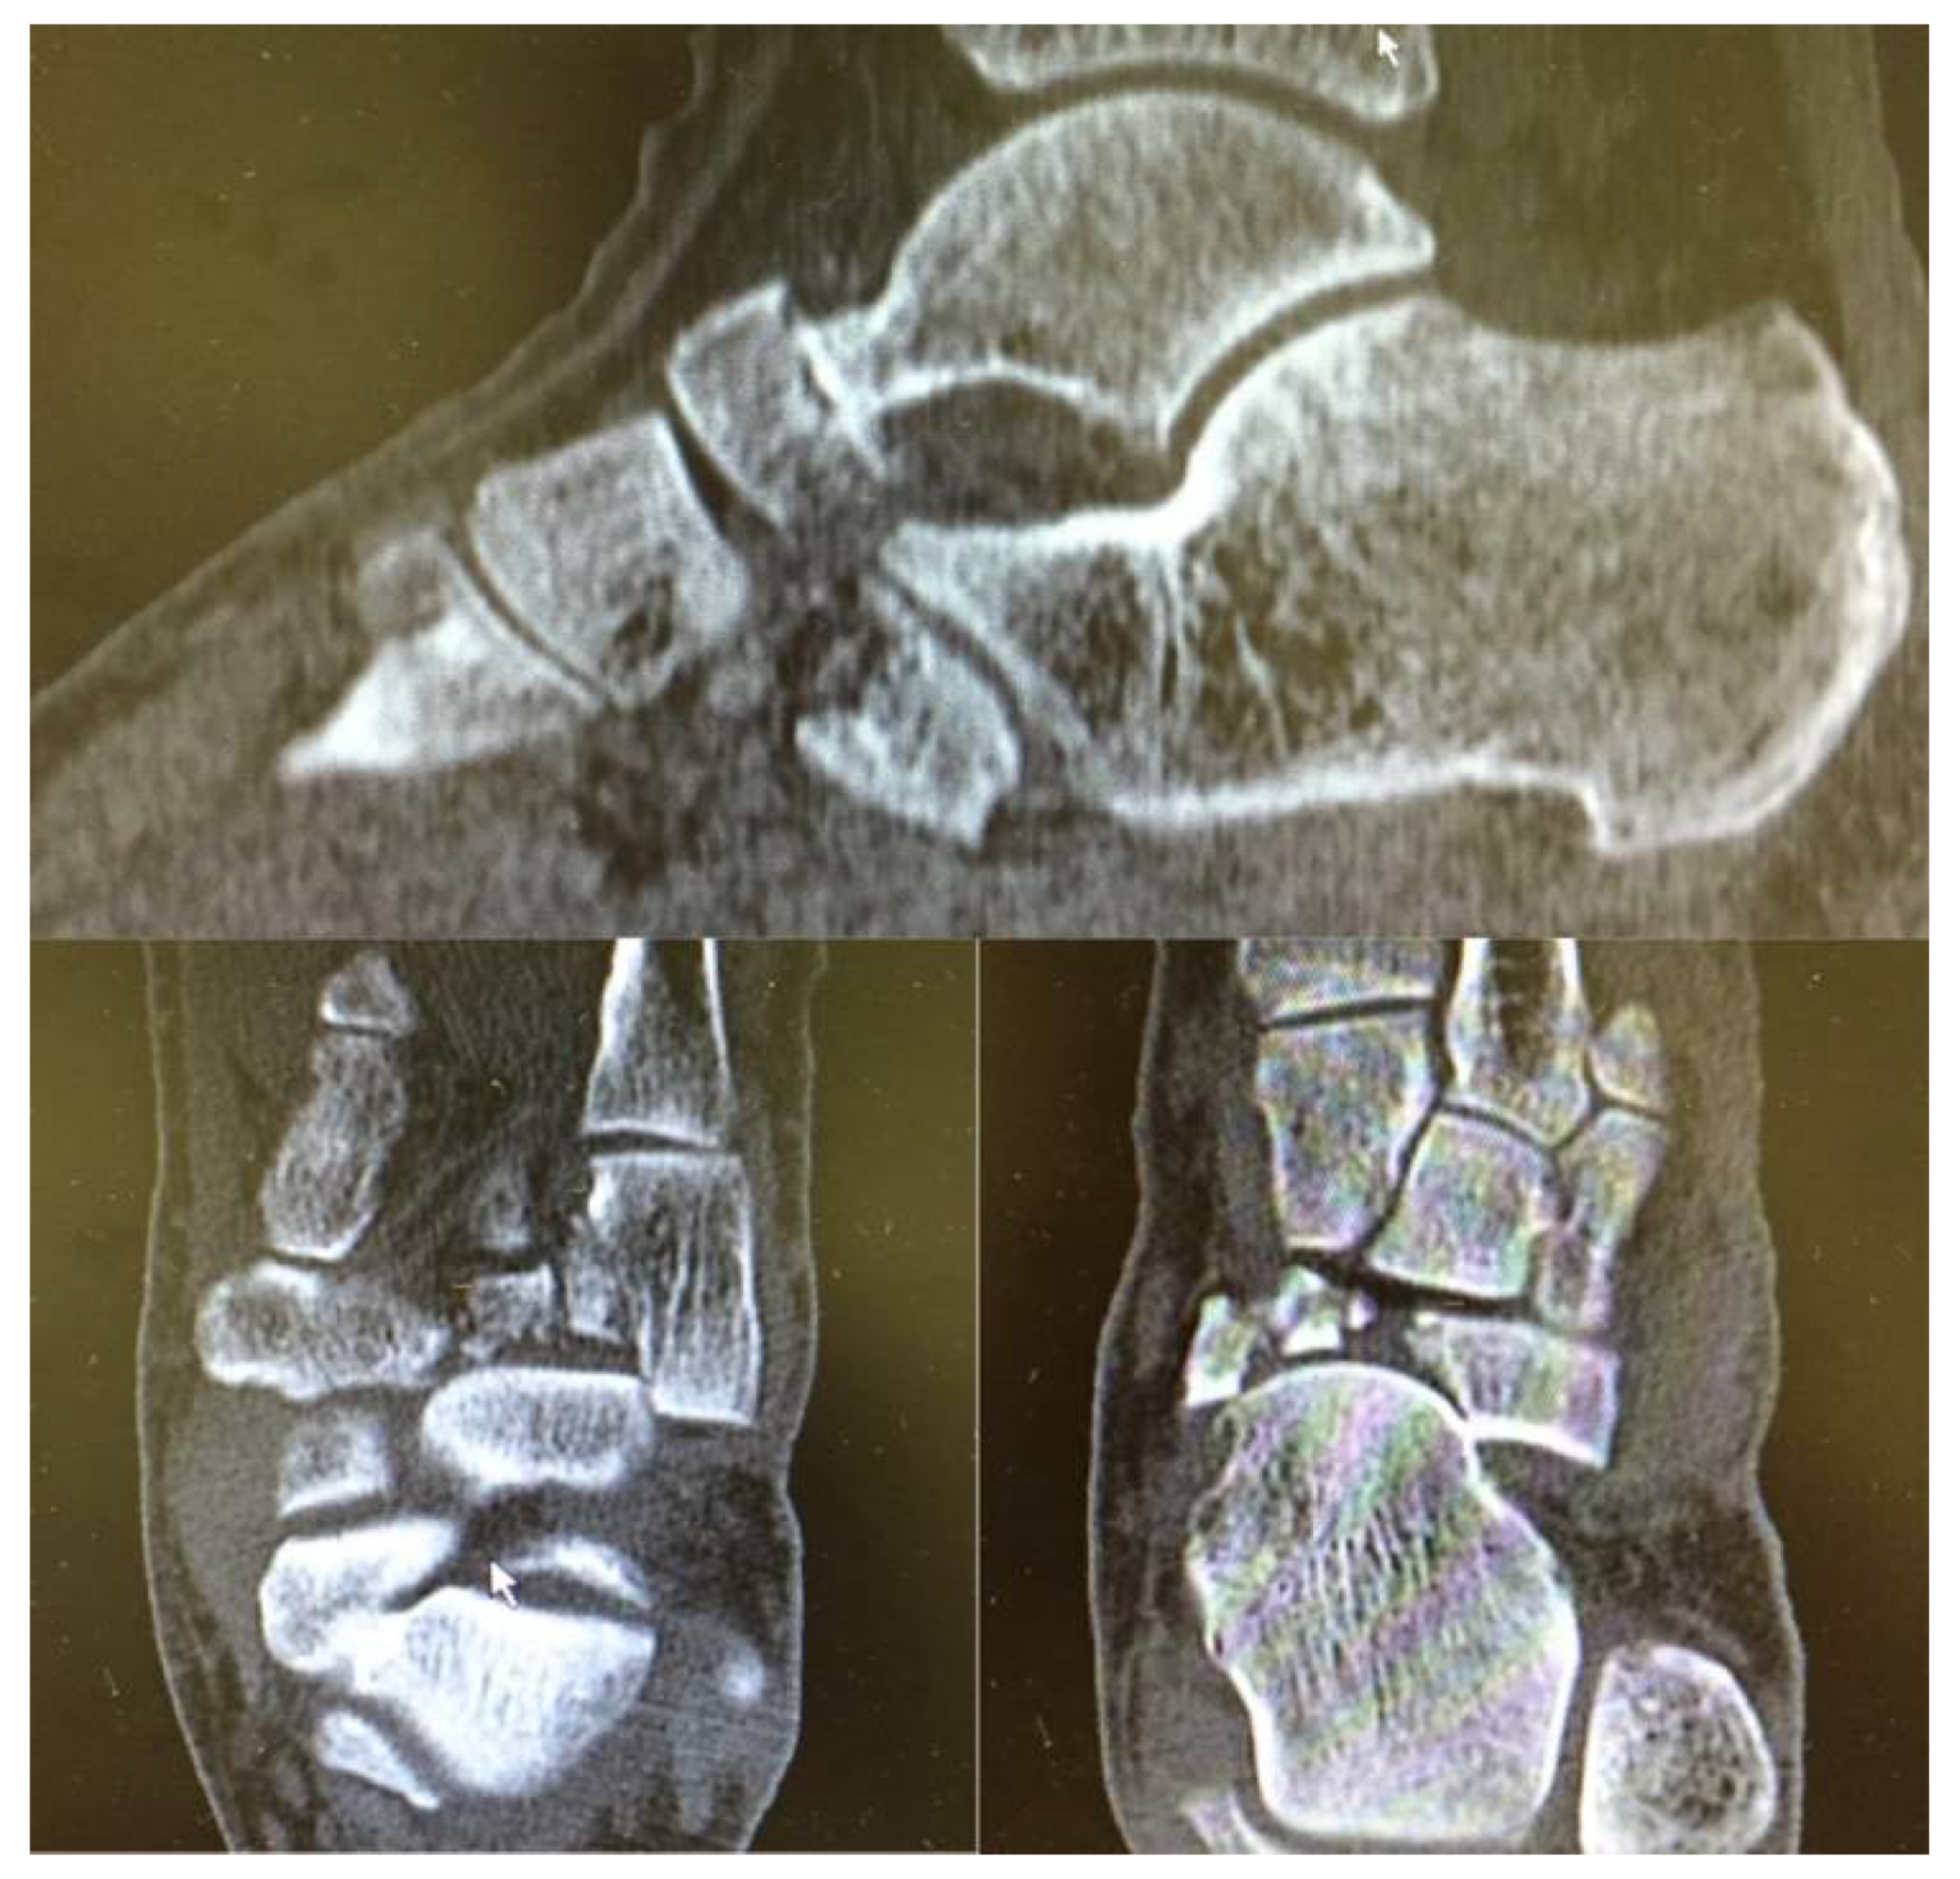

2. Case Presentation